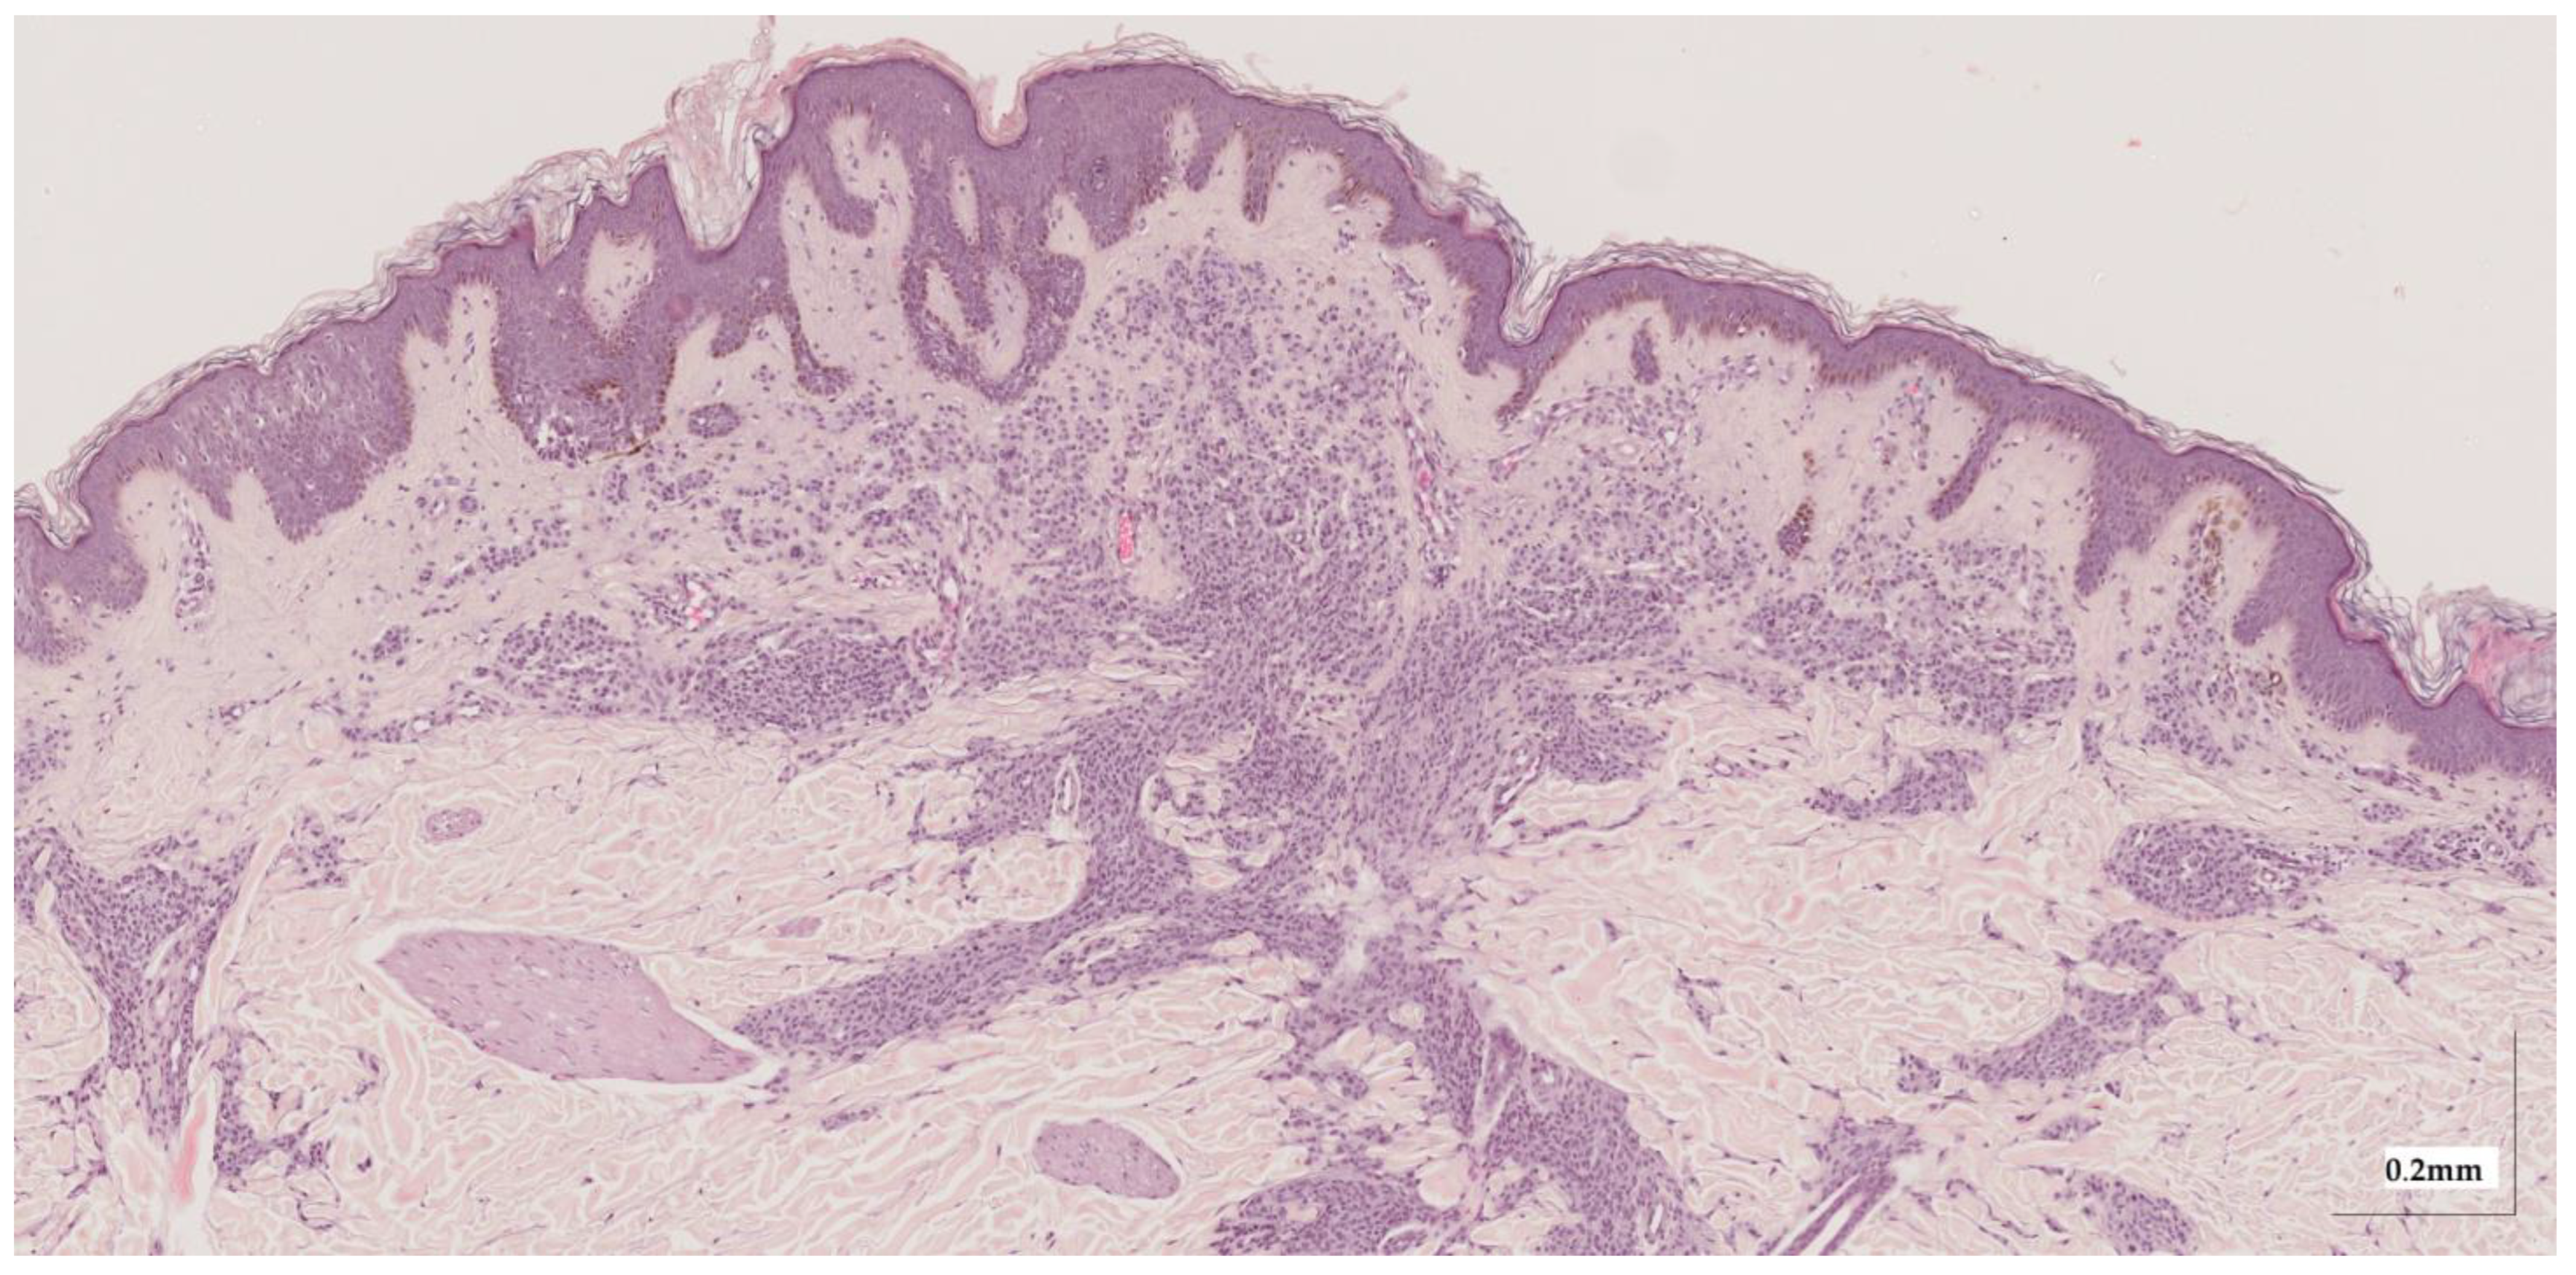

Appendix A. Selected Cases Studies’ HE Histopathological Images (Limited to OCT FOV)

| Compound nevus (CN) Case 1 | Localization: right dorsal |

![]() | ![]() |